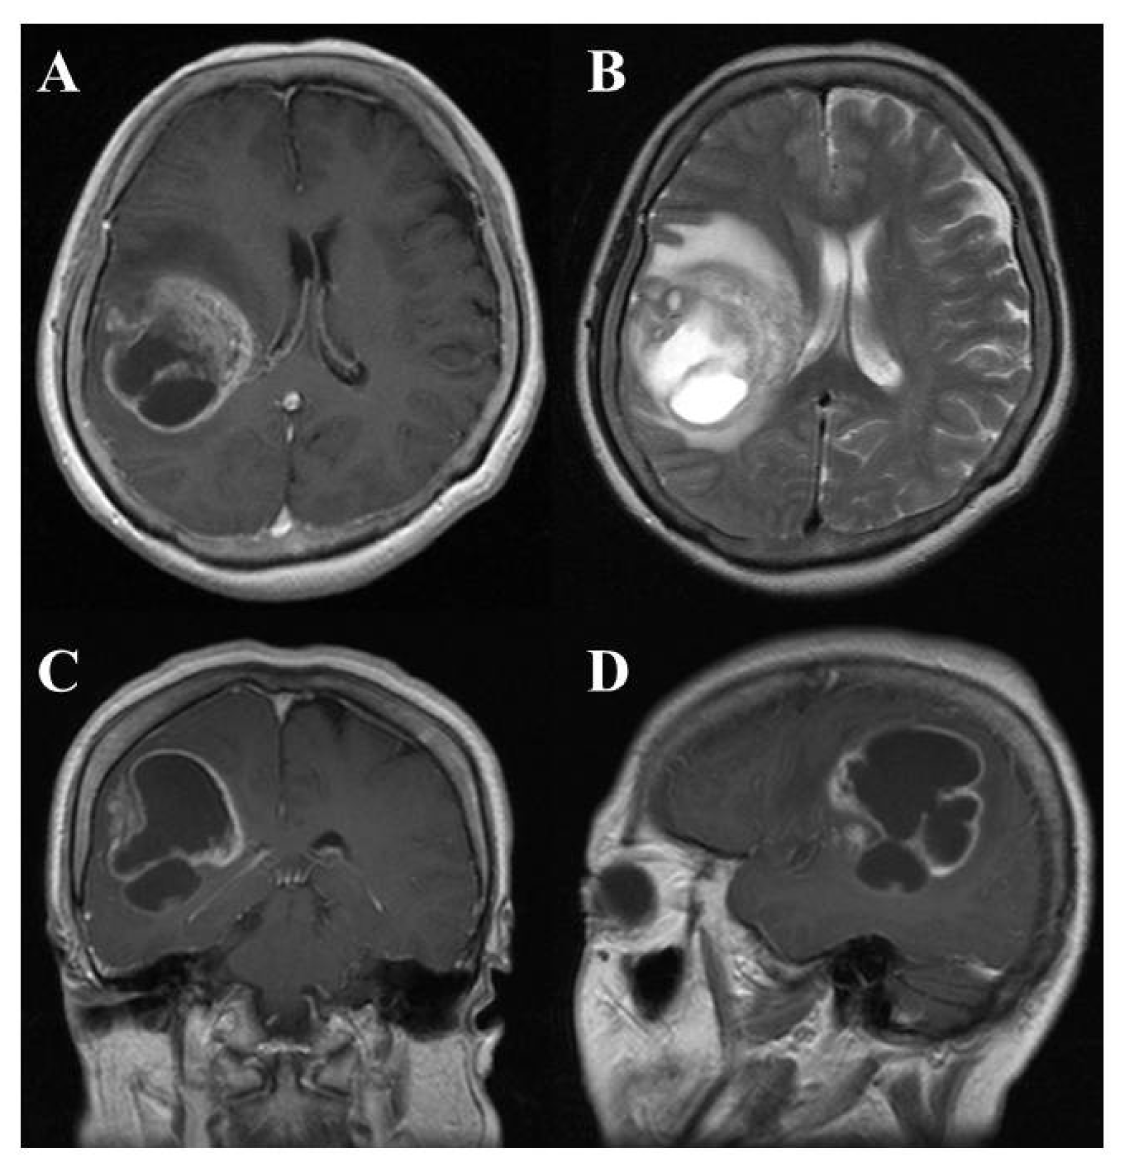

On computed tomography (CT) and magnetic resonance imaging (MRI), many GBMs present a typical appearance of ring enhancement indicating a central necrosis surrounded by enhancing viable tumor (Figure 1). Peritumoral edema, usually with distortion of the surrounding brain and ventricles (mass effect), is well visualized by MRI. Despite the typical appearance, other enhancing lesions within the cerebral hemisphere, especially abscess, metastasis, lymphoma, or even acute multiple sclerosis plaques and subacute infarctions, should be considered as notable differential diagnoses.